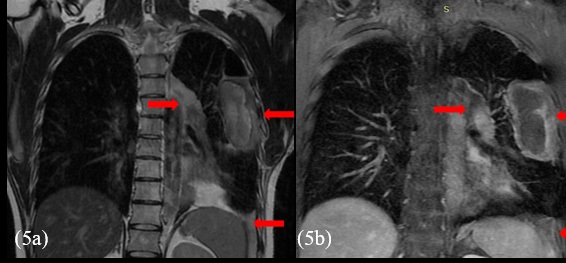

Before opting for some new agent, empirically, a next generation sequencing analysis was performed on the primary tumor tissue, to guide the subsequent therapy. An amazing pathogenic HMBOX1-ALK gene fusion was identified. Thus, we decide to continue his treatment by administering crizotinib, a tyrosine -kinase inhibitor (TKI) approved in Brazil for usage in lung cancer with ALK translocation. At the beginning of oral therapy, he manifested nausea grade 2, vomit grade 1 and diarrhea grade 2, according to WHO (World Healthy Organization) profile toxicity; all of these symptoms were manageable with regular antiemetic drugs and loperamide. Approximately, one month after the beginning of the new treatment, he reported reduction of chest pain and cough, as well as diminishing of tiredness and dyspnea, which were present only with great effort. The evaluation images with 45 days of crizotinib therapy showed reduction of all the lesions with appearance of necrotic/hemorrhagic areas (Figures 5a and 5b).

Figure 5: Thoracic MRI shows shrinkage of the extent and reduction of the post-contrast enhancement of the lesions (arrows) and appearance of hemorrhage intralesional content (not shown). The biggest one measured 8.5 x 4.0 x 8.0 cm - 140 cm³ (before therapy this value was 11.0 x 6.0 x 11.0 cm - 375 cm³; the others measured 6.0 x 2.5 x 4.0 – 30 cm³, and 6.0 x 5.0 x 2.5 cm - 40 cm³ (before therapy they measured 8.0 x 3.5 x 6.5 cm - 95 cm³, and 7.0 x 7.0 x 3.0 cm - 75 cm³, respectively).